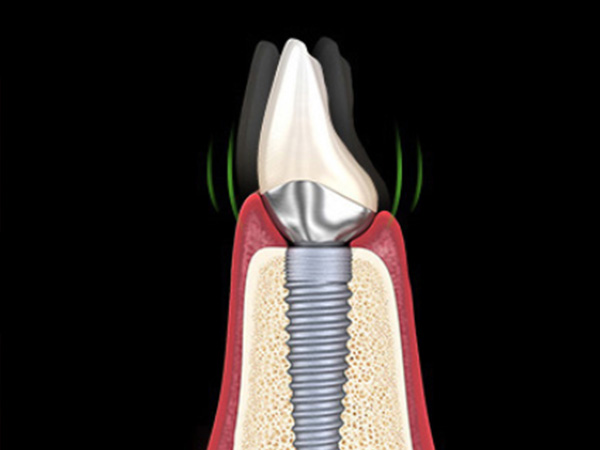

임플란트 주변이 자주 붓거나 통증이 반복되고, 양치 후 피가 나거나 잇몸이 자꾸 붉게 부어오르는 경우 재수술을 고려할 수 있습니다.

씹을 때 임플란트가 흔들리거나, 엑스레이 상에서 뼈가 많이 녹아 있는 것이 확인될 때에도 추가 치료 또는 재수술이 필요할 수 있습니다.

나사 풀림, 나사 파절, 보철물이 반복적으로 깨지는 경우에는 구조적인 문제를 동반한 경우가 많아, 단순 수리보다 재계획이 중요합니다.